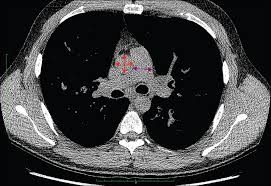

Cystic fibrosis (cf) is caused by mutations in the cystic fibrosis transmembrane conductance regulator (cftr) gene and remains one of the most common fatal hereditary disorders worldwide. Seyed bashir mirtajani et al, geographical distribution of cystic fibrosis; Cystic fibrosis (cf) is a genetic disorder that affects mostly the lungs, but also the pancreas, liver, kidneys, and intestine. Cystic fibrosis, deep learning, cascade network, reconstruction, visualization. Care guidelines for nutrition management.

Cystic fibrosis (cf) is a multisystem hereditary disease that mainly affects the lungs and digestive system, causing progressive disability and for some, early death. Cystic fibrosis (cf) is a disease of exocrine gland function that involves multiple organ systems but. Severe stromal fibrosis, plethora, hypertrophy of muscle. Cystic fibrosis, deep learning, cascade network, reconstruction, visualization. Cystic fibrosis is an autosomal recessive disorder, and most carriers of the gene are asymptomatic. Cystic fibrosis (cf) is a genetic disorder that affects mostly the lungs, but also the pancreas, liver, kidneys, and intestine. Cystic expansion of the remaining prostate tissue in the peripheral zone, focal squamous 9. Care guidelines for nutrition management. Transurethral resection of the prostate. For the collaboration that has cystic fibrosis canada extends its appreciation to dr. Hypoplasia of the sphenoid sinuses as a diagnostic tool in cystic fibrosis. The past 70 years of data analysis, 2017. Read about the symptoms, causes and treatments.